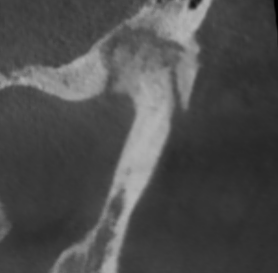

Перед началом лечения я провожу часовую первичную консультацию. Для этой встречи вам необходимо сделать «МРТ ВНЧС» и «КЛКТ двух челюстей с захватом ВНЧС в привычном прикусе».

Во время консультации мы смотрим и анализируем ваши исследования. Я подробно объясняю строение ВНЧС, показываю все причинные факторы вашей проблемы, отвечаю на все вопросы «Почему?»